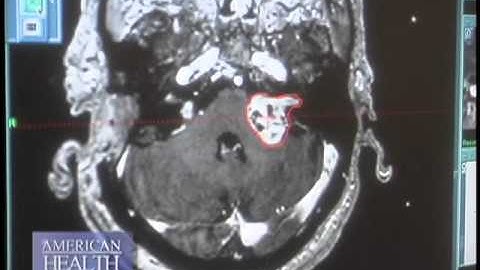

Brain mapping